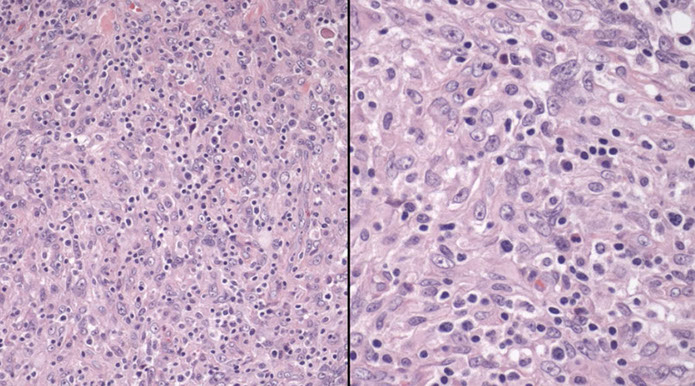

Micro: LN c diffuse nodal involvement showing pseudofollicular architecture (no true mantle zone) c large pale prolif centers c prolymphocytes (>11%; sm to med size cells c clumped chromatin and small nucleoli), paraimmunoblasts (larger, c round to oval nuclei, central red nucleoli)

- 11-55% prolymphs = CLL/PLL

Smudge cells seen in PB with small lymphs c clumped chromatin and round nuclei

- lots of prolymphocytes in PB = poor px (>55% prolymphs = B-cell prolymphocytic leukemia (B-PLL)

CLL pseudofollicle (proliferation center). Little lymphocytes with small cytoplasm on the left. On the right, paraimmunoblasts are larger, with a little more cytoplasm, with prolymphocytes (black arrow)showing dispersed chromatin, and the red arrow to paraimmunoblasts with prominent central nucleolus (called "paraimmunoblasts" because typically smaller than B-type immunoblasts).

LASOP lecture Dr Reichard, 1/18/2020